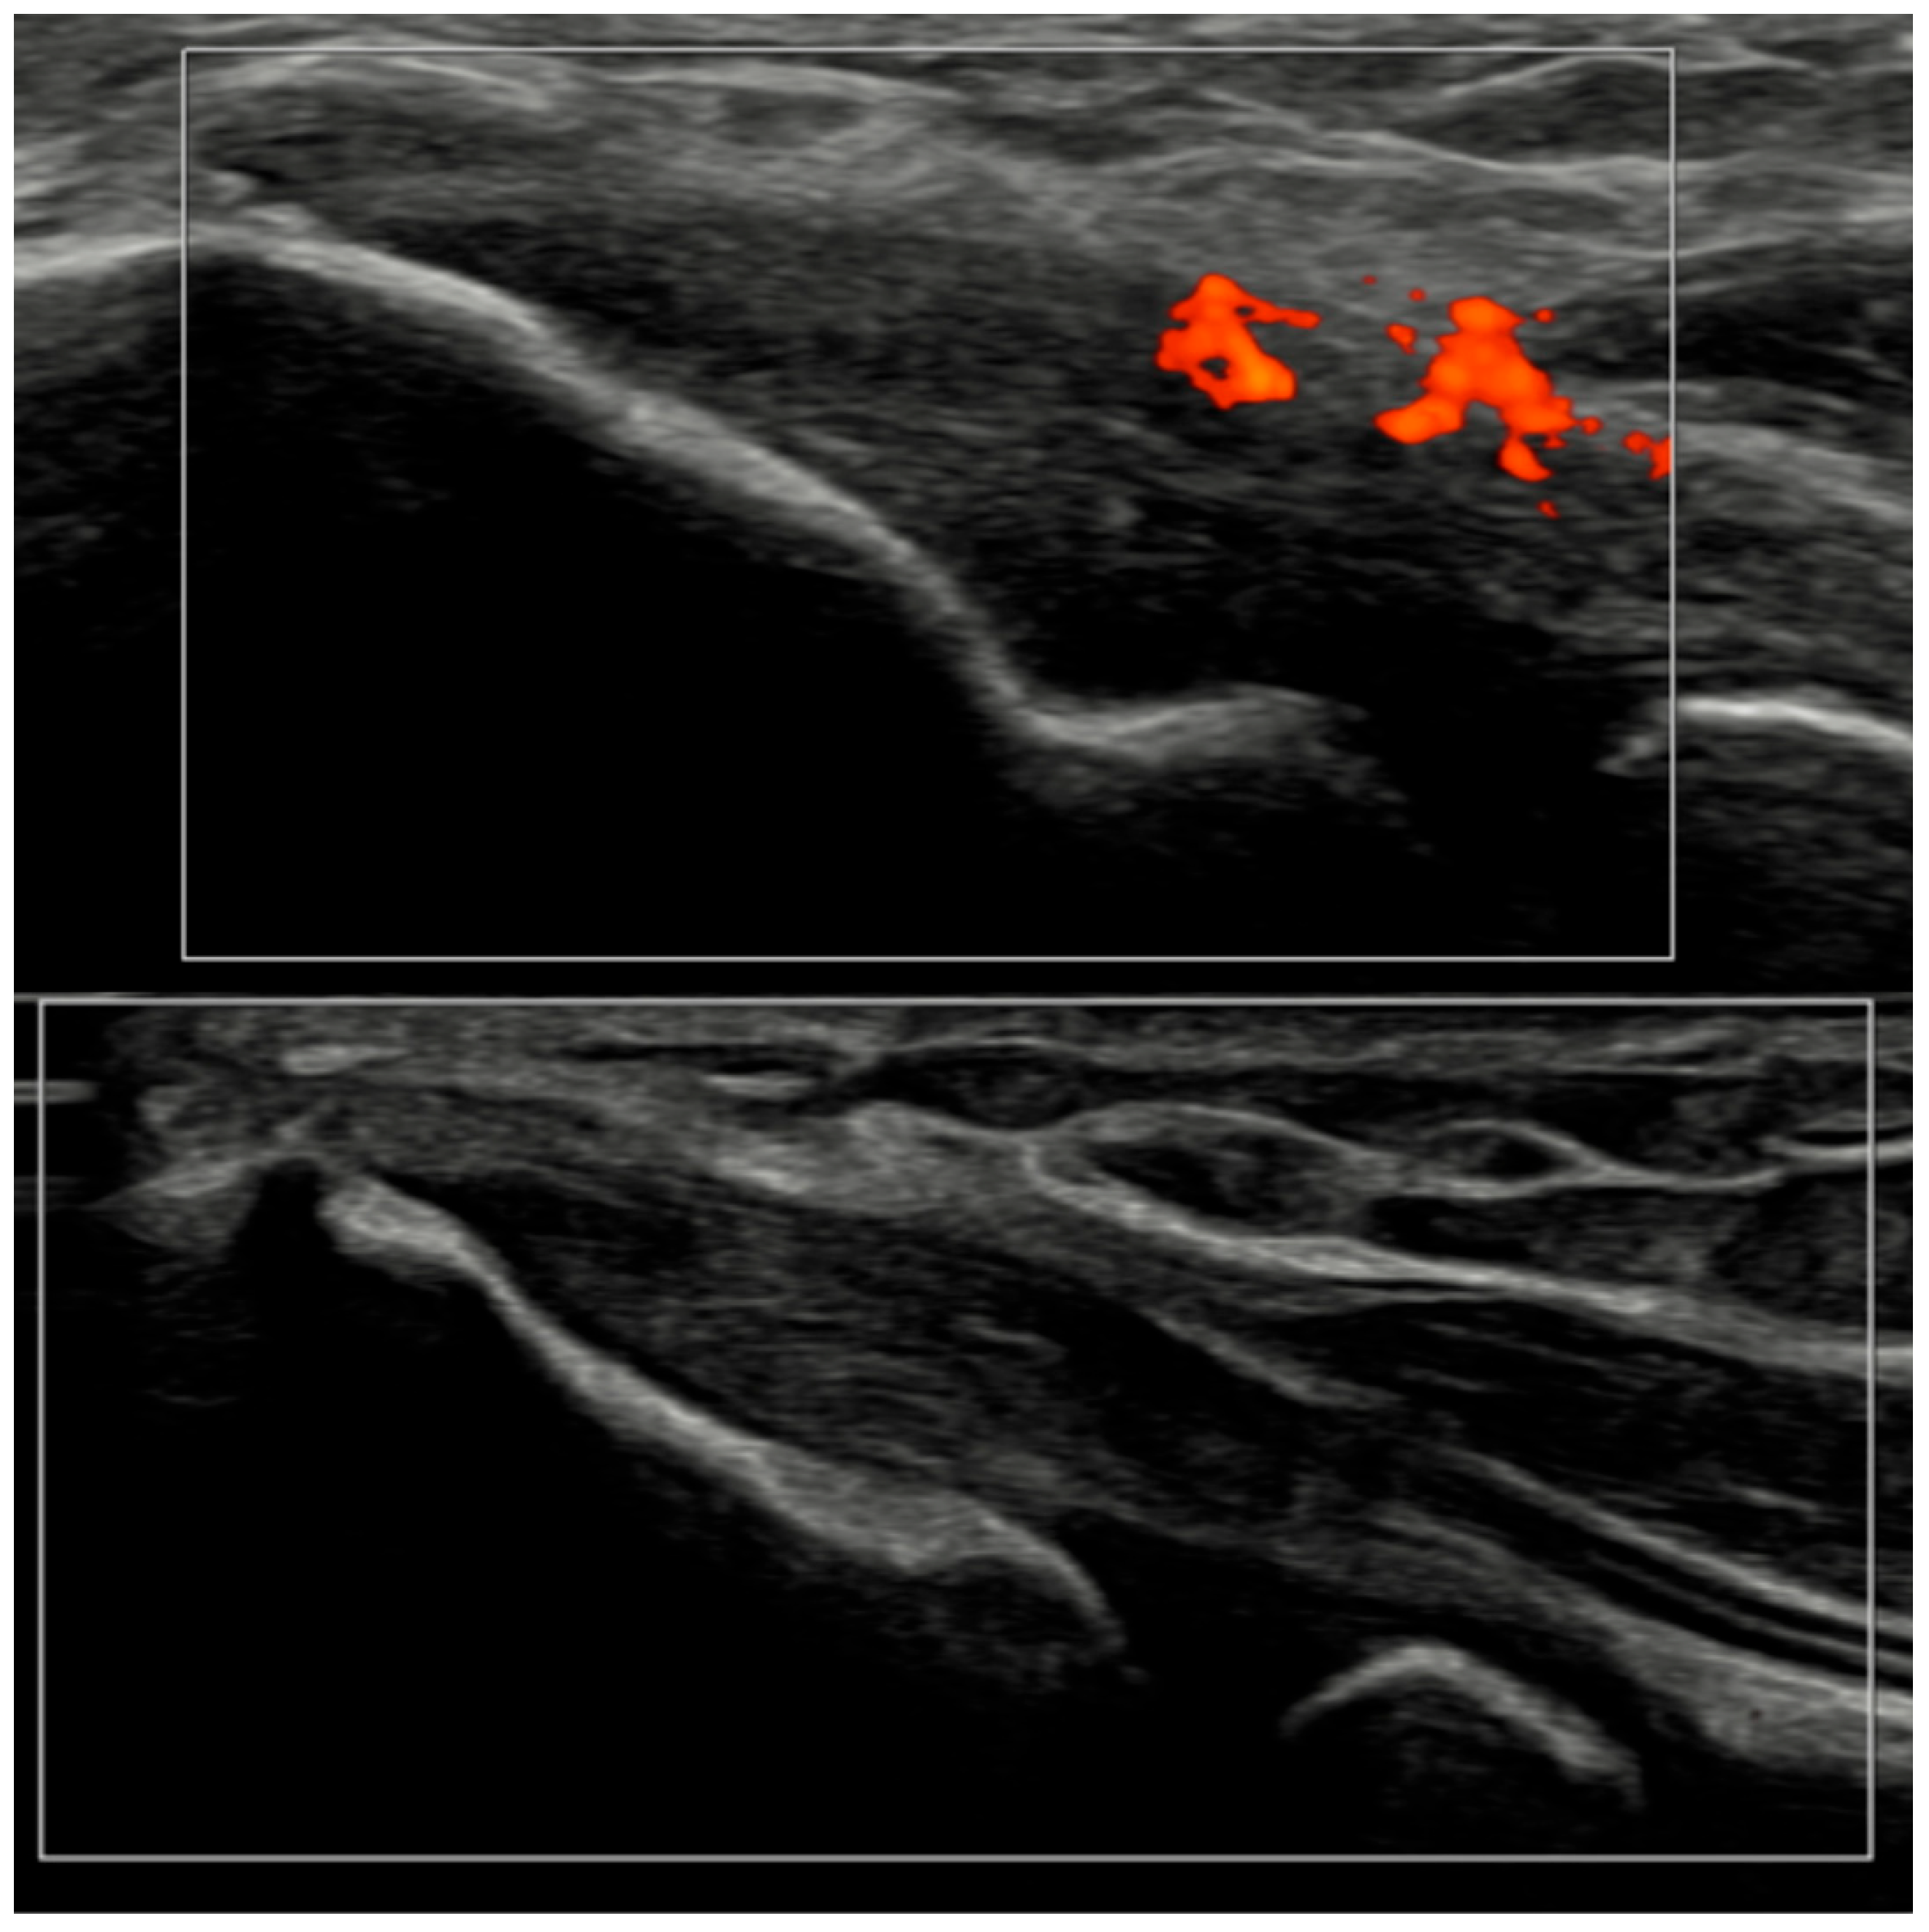

Several methodological and technical features add credibility to these results. All ultrasound acquisitions were performed on calibrated high-frequency systems using low-PRF Doppler settings per EULAR standards, minimizing artifacts such as anisotropy or compression-induced flow suppression [3]. The synovio-entheseal complex model of PsA pathogenesis provides a conceptual basis for our findings: the anatomical continuity of synovitis, tenosynovitis, and enthesitis explains why vascular suppression under IL-23 blockade manifests coherently across tissues. Representative ultrasound images (Figure 4, Figure 5, Figure 6 and Figure 7) illustrate this evolution at prototypical sites such as the wrist and elbow extensor enthesis. However, mini-entheses of the hand and nail unit were not systematically evaluated; future guselkumab imaging cohorts should incorporate these distal targets, given their diagnostic and prognostic specificity [3].

Figure 4.

Longitudinal ultrasound image of the PIP III joint showing synovial hypertrophy (grade 2) and intra-articular power Doppler signal with distal capsular and entheseal extension (PD grade 2), corresponding to a combined EULAR–OMERACT synovitis grade = 2 (joint level).

Figure 6.

Longitudinal ultrasound comparison of the wrist joint at baseline (T0, top) showing synovial hypertrophy (grade 2) with intra-articular power Doppler signal (PD grade 2), corresponding to a combined EULAR–OMERACT synovitis grade = 2 (joint-level), and at 6 months (T6, bottom), demonstrating near-complete resolution of synovial hypertrophy and power Doppler signal, with a joint-level EULAR–OMERACT synovitis grade = 0.

Figure 7.

Ultrasound images of the elbow extensor enthesis at baseline (T0, top image) showing power Doppler signal (PD grade 2), and at 3 months (T3, bottom image), demonstrating resolution of power Doppler signal (PD grade 0).